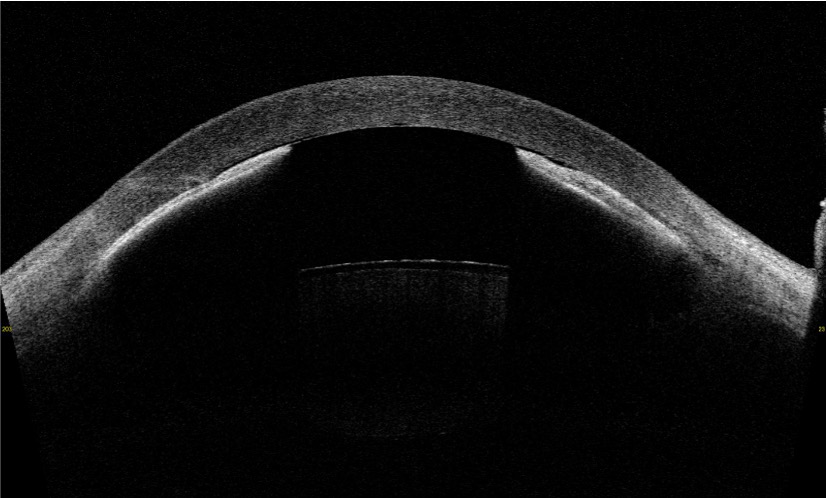

AS-OCT scan demonstrating forward bowing of the iris with iridocorneal touch following implantable collamer lens (ICL) removal. The anterior chamber appears markedly shallow, with the iris contour displaced anteriorly and contacting the posterior corneal surface, indicative of post-operative angle crowding and anterior segment configuration changes.

CASIA2: Anterior Segment 3D Swept-Source OCT